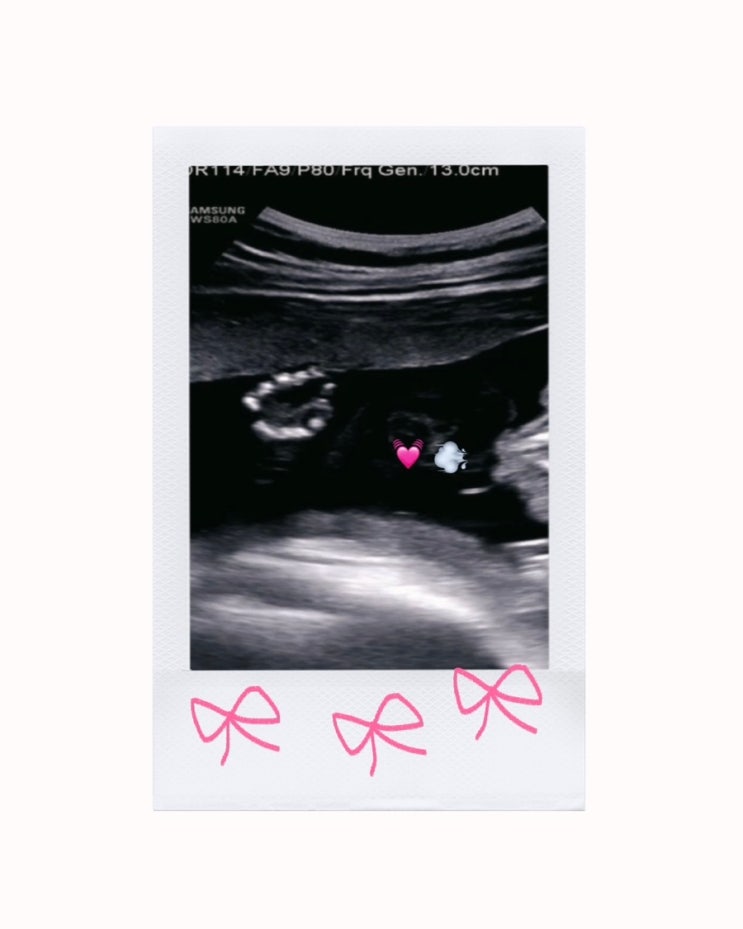

임신 22-23주차 : 정밀초음파를 보고 왔다? • 체중조절 • 급격한 체력저하?

[ 임신 22-23주차 : 22-23w 임신기록 ] 정밀초음파를 보고 왔다? • 체중조절 • 급격한 체력저하? ...